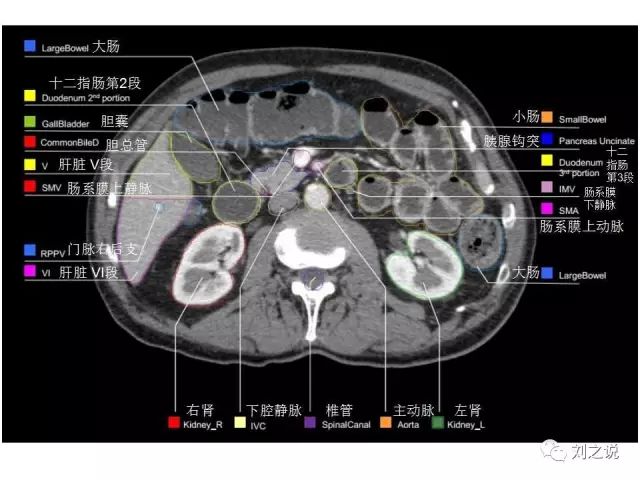

参考RTOG共识和3D-body解剖。

来源:刘之说